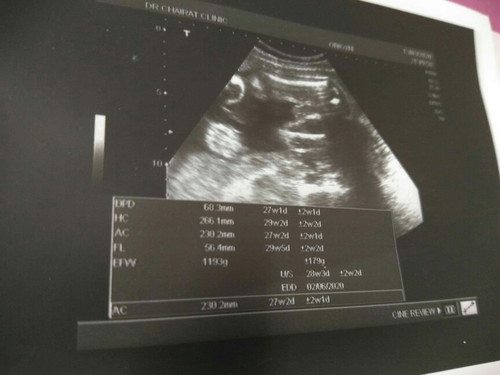

ผลอัลตร้าซาวด์ 27week's 5day กำหนดคลอด8มิ.ย

หลังจากที่ลุ้นมาตลอดว่าจะได้ลูกสาวหรือลูกชาย วันนี้ทราบผลอย่างเป็นทางการ ลุงหมอคอนเฟิร์ม มาแล้วจ้า อ้าขาโชว์หนอนน้อยเต็มที่เลย? แถมน้ำหนักดีงาม 1193g ปกติ เกินเกณฑ์ ขอดูภาพซาวด์ของแม่ๆบ้านอื่นหน่อย อิแม่เพลีย เพราะอยากได้ลูกสาว เพราะท้องนี้ท้องที่3แล้ว คนพี่ก็ลูกชายทั้ง2 สรุปชาย3จ้ะแม่จ๋า อวสานโลก???